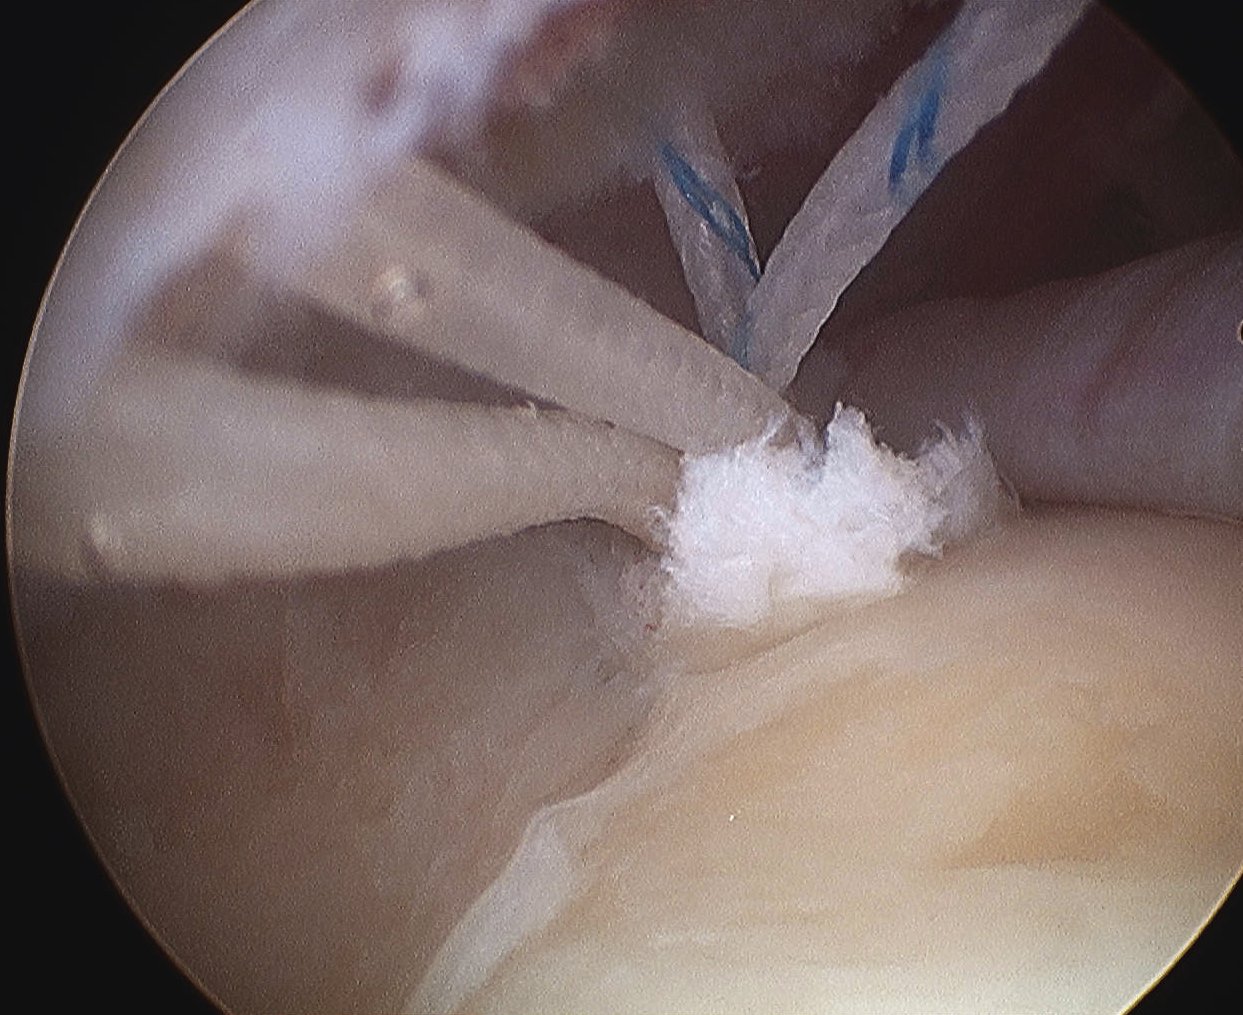

Trans-tendinous repair

Arthroscopic PASTA technique

Technique

Camera in glenohumeral joint

- debride insertion onto footprint

- 5mm anchor passed through musculotendinoous junction into footprint

- use birds beak suture to retrieve sutures / suture shuttle using spinal needle

- tie in subacomial space